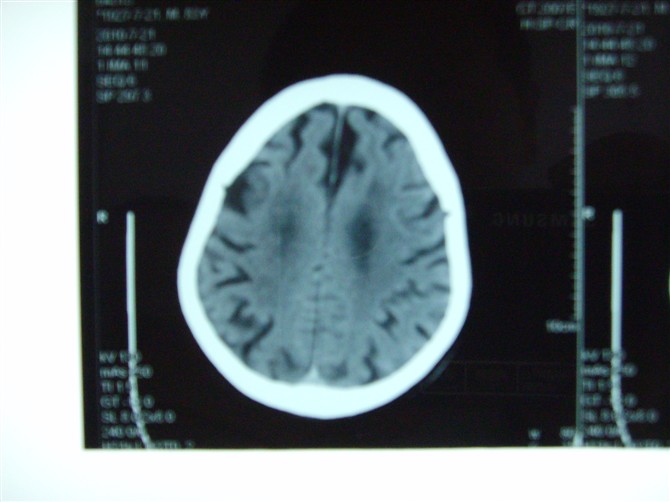

标题: CT27993:男 83岁 头晕伴双下肢无力一天 [打印本页]

标题: CT27993:男 83岁 头晕伴双下肢无力一天

脑萎缩。伴小脑齿状核、苍白球钙化。必要是mri进一步检查。

脑白质疏松症,脑萎缩,复查

脑萎缩

脑萎缩。伴小脑齿状核、苍白球钙化.脑白质脱髓鞘病变

脑白质变性、脑萎缩。甲状旁腺功能减退。

脑白质疏松症,脑萎缩!

老年脑改变

脑萎缩,脑白质疏松症。

1)双侧小脑半球脑软化灶。2)全脑萎缩。3)脑白质病。